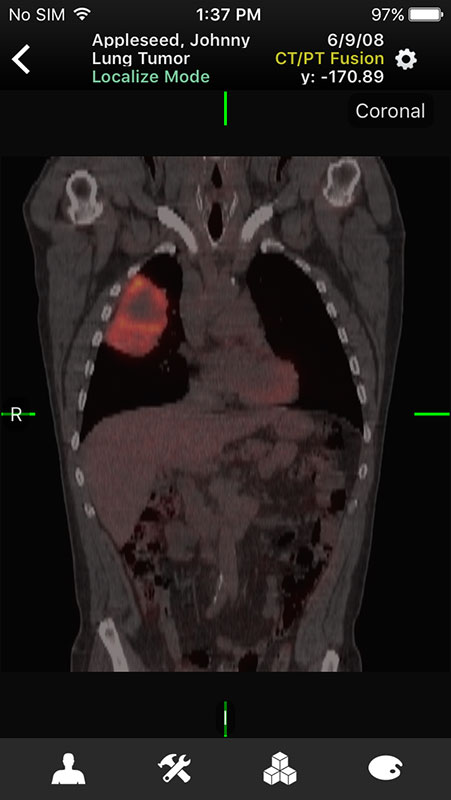

These sample images feature same imaginary patients and cases from the Mobile MIM app and contain X-ray, PETCT, MR, and ultrasound scans, alongside the name of the procedure.

Just like in Mobile MIM app, images open in multi-planar view allowing users to choose series depending on the type of imaging technique, add annotation, or measure the image.

- Provides multi-planar view